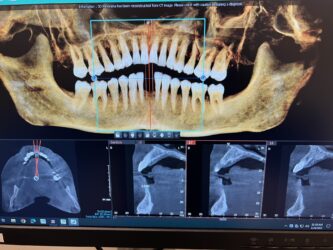

Hi! I have a case I wanted some feedback on. Pt is interested in replacing 24 and 25 with implants. I have attached the cbct below and was wondering what you guys think as far as tx planning. I wanted to place 1 implant with a cantilever for 24 and 25. How would you plan the case given the thin bone? Alveoplasty? GBR? Thank you